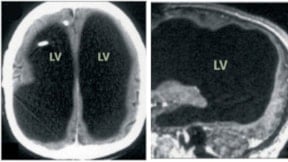

Daily Mail’de yer alan habere göre; Dr. Romina Dibra, beyin tümörü belirtilerinin çoğunun, büyüyen tümörün kafatası içindeki basıncı artırmasıyla ortaya çıktığını belirtti. “Kafatası kemikten oluştuğu için büyüyen bir tümör, iç basıncı artırır. Bu duruma kafa içi basınç artışı (intrakraniyal basınç) denir,” diye açıklayan Dr. Dibra, bunun baş ağrısı, uyku hali, kusma ve görme problemlerine yol açabileceğini söyledi.

Dibra, kafa içi basıncın artmasının beyne olan kan akışını azaltabileceğini ve bunun sonucunda kişinin bilinç kaybı veya aşırı uyku hali yaşayabileceğini belirtti. Ayrıca kusma ve mide bulantısının da olası belirtiler arasında yer aldığını ancak bu semptomların genellikle diğer belirtilerle birlikte ortaya çıktığını söyledi.

Beyin kanseri tedavisi, tümörün türüne ve konumuna bağlı olarak değişiklik gösteriyor. Genellikle cerrahi müdahale ilk seçenek olurken, ardından radyoterapi ve bazı durumlarda kemoterapi uygulanabiliyor. Tümörün beyne baskısını azaltmak için steroidler, nöbetleri kontrol altına almak içinse anti-epileptik ilaçlar reçete edilebiliyor.